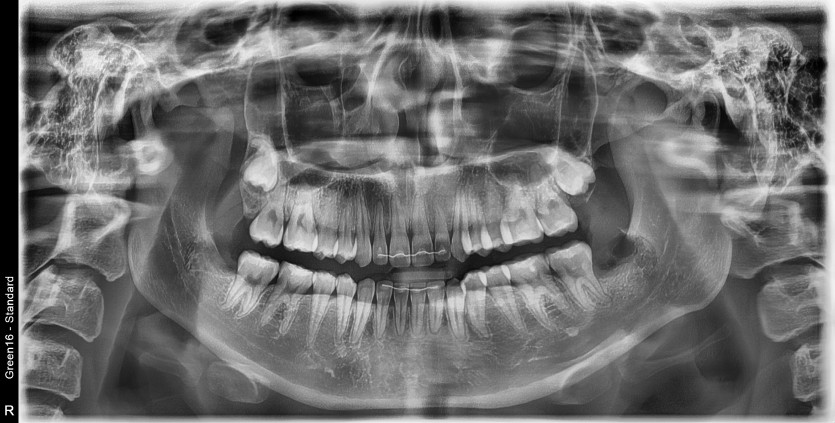

#38,48 사랑니 발치

구강 외과 전문의가 당일 발치했습니다.